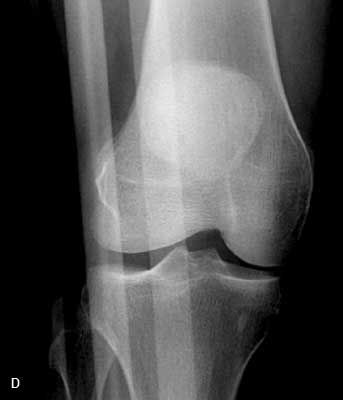

Outcome of this case. The patient'sdislocation was reduced externally.A frontal radiograph of the kneeobtained after the reduction showsnormal alignment of the patella andthe distal femur (D). This is confirmedby a post-reduction lateral view (E).At 3 months, the patient has not hada recurrence.